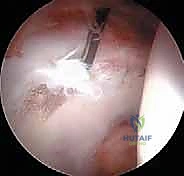

الخطوة 3: الاستكشاف بكاميرا 4K

يتم إدخال منظار مزود بكاميرا عالية الدقة (4K) وإضاءة قوية. تُعرض الصورة مكبرة على شاشة أمام الجراح، مما يسمح له برؤية أدق تفاصيل الغضروف والشفا الحقي بوضوح يفوق الرؤية بالعين المجردة.

الخطوة 5: إصلاح الشفا الحقي (Labral Repair)

إذا كان الشفا الحقي ممزقاً (وهو أمر شائع جداً)، لا يتم استئصاله، بل يحرص الدكتور هطيف على إصلاحه للحفاظ على وظيفة المفصل. يتم ذلك باستخدام "خطاطيف خياطة" (Suture Anchors) صغيرة جداً تُزرع في العظم وتُستخدم لربط وخياطة الشفا وإعادته لمكانه الطبيعي.